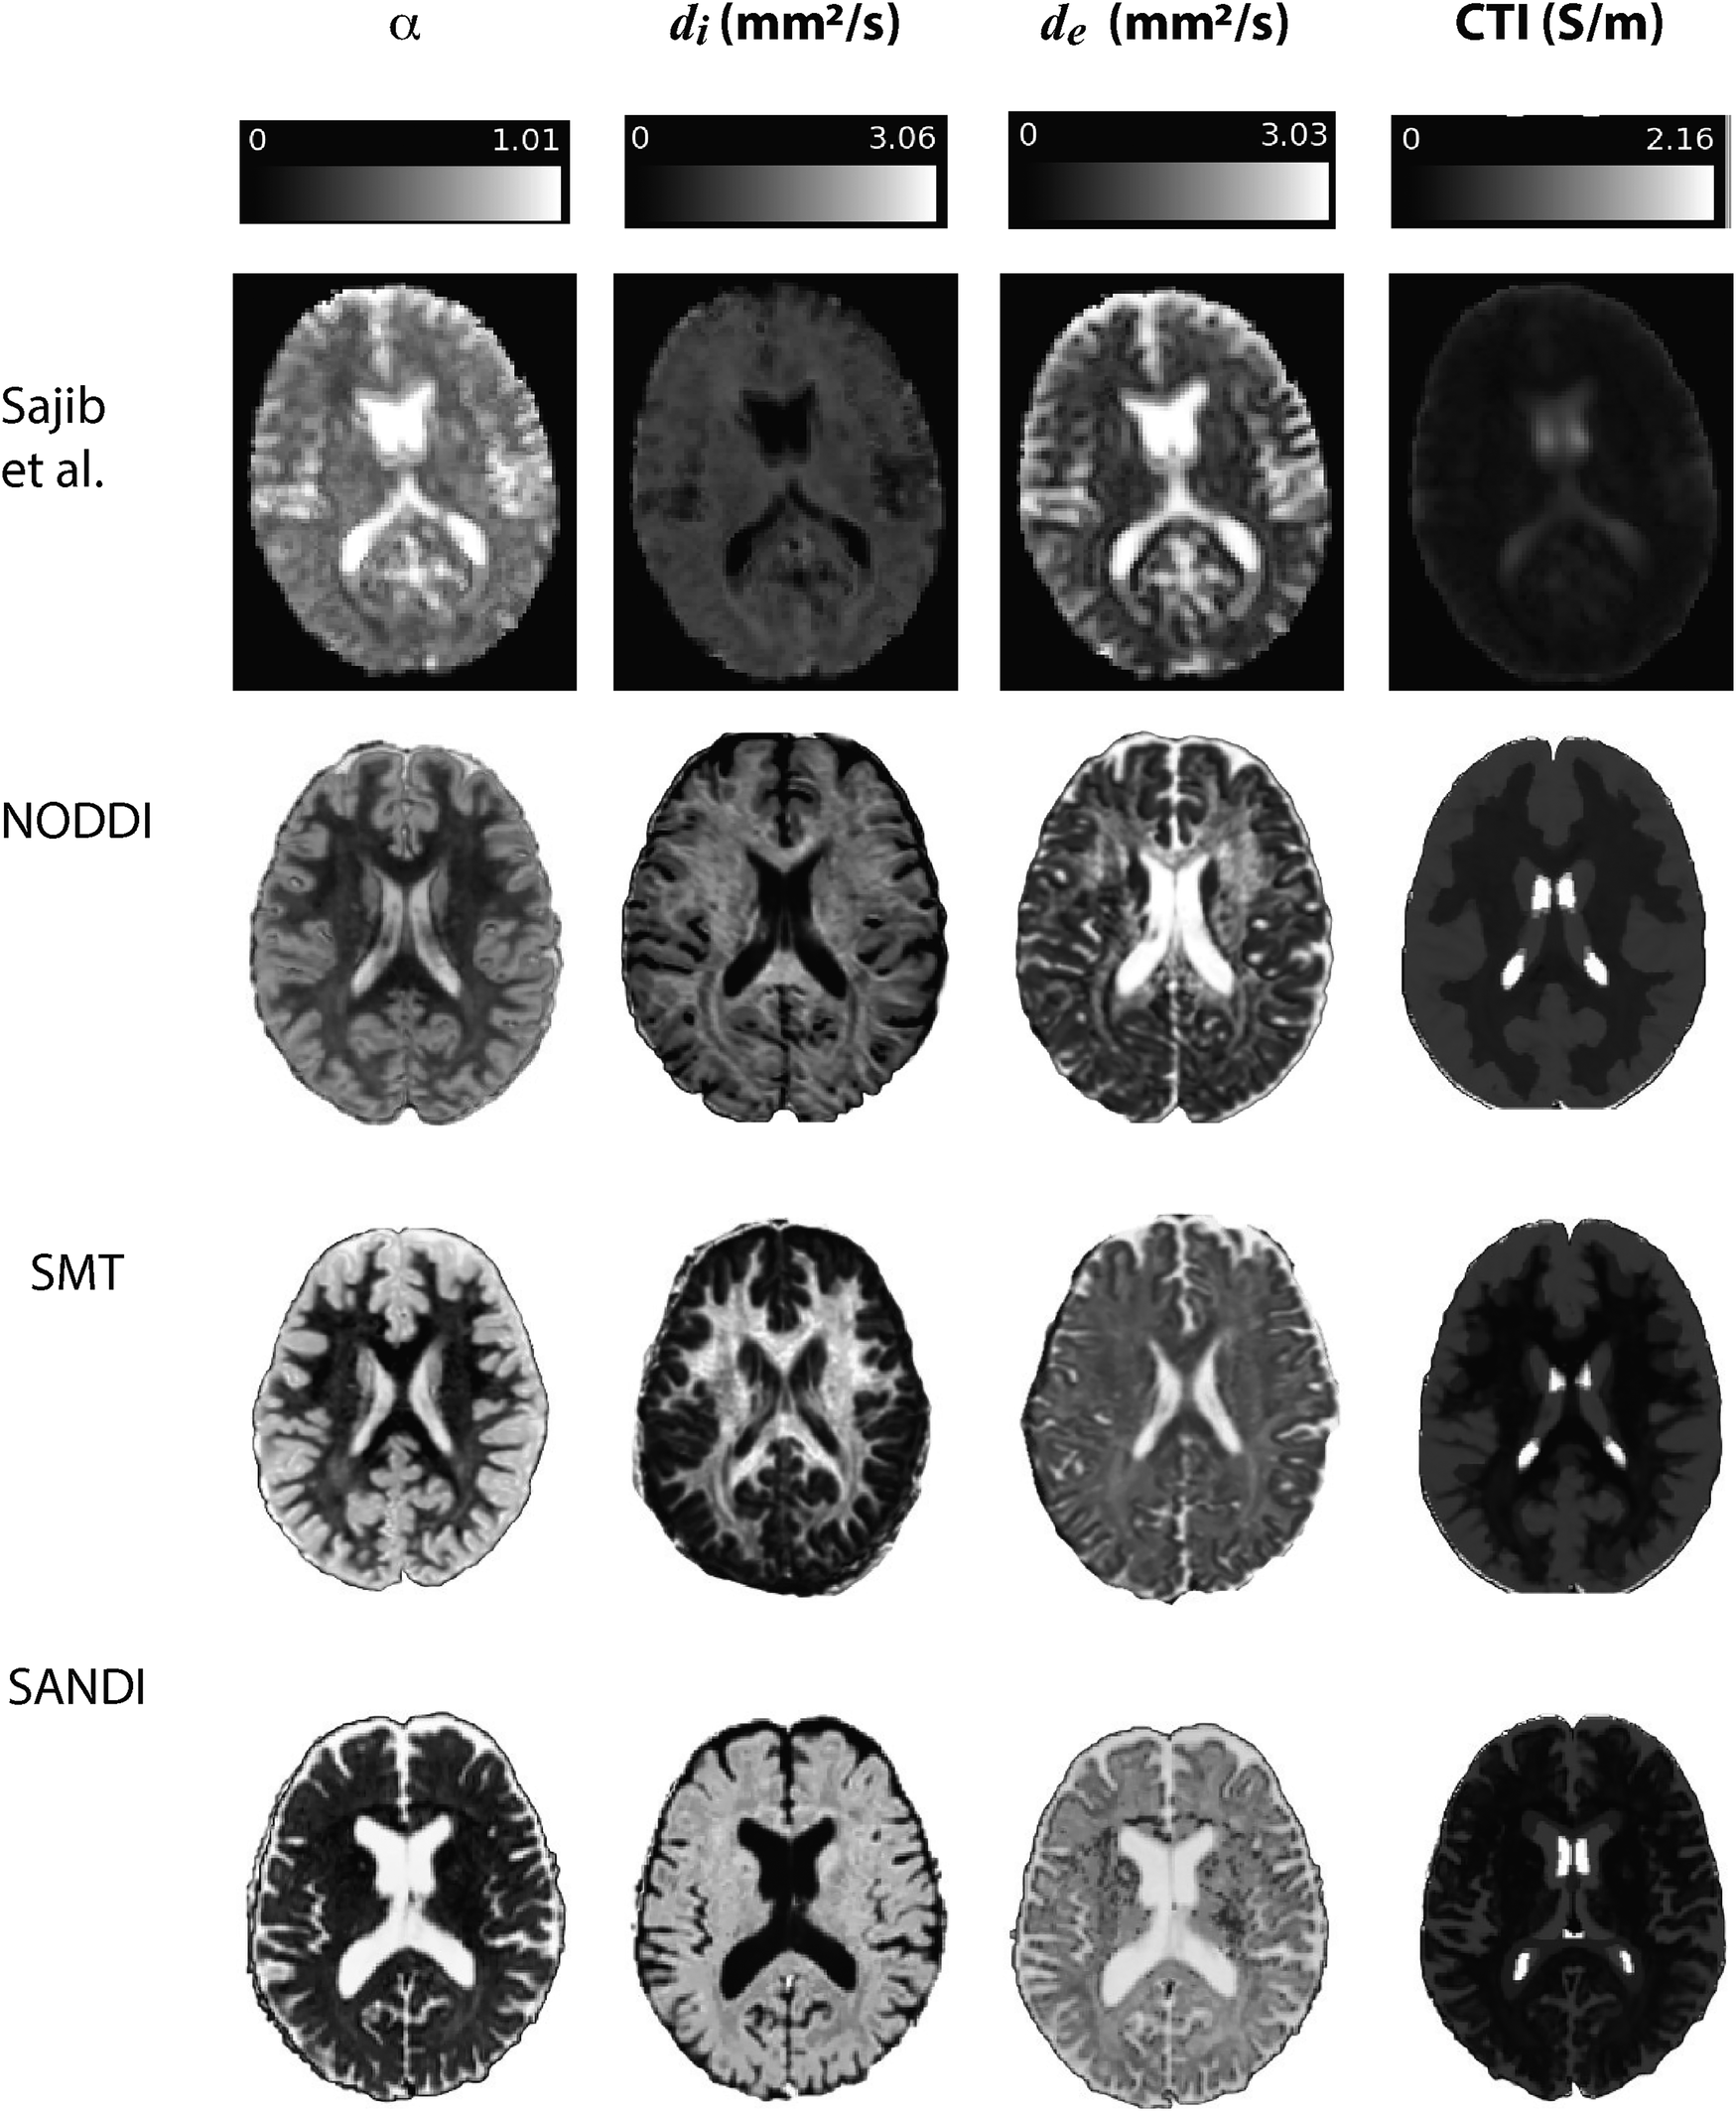

Examples of contributing parameters and low-frequency conductivities predicted by each method are displayed in Figure 3 for individual subjects. Also shown in this figure is an example of parameters and low frequency conductivity found in vivo by Sajib et al. (26). Note that the data slice and subject used to determine the example NODDI, SMT and SANDI parameters was the same slice of MNI space in each case, while that shown in the Sajib. et al data was estimated over a different, 5 mm slice. Differences between parameters estimated by each method were clearly evident, with α values estimated in both gray and white matter being larger in NODDI and SMT methods than in SANDI, and di appearing larger in SANDI than for other methods. Overall, gray and white matter conductivities predicted by the NODDI method were larger than those predicted with SANDI, with SMT predictions sitting between these two.

Figure 3

www.frontiersin.org

Figure 3. Comparison of results found in Sajib et al. (26) in a single subject against example α, di and de quantities extracted for individual subjects in NODDI, SMT and SANDI analyses.